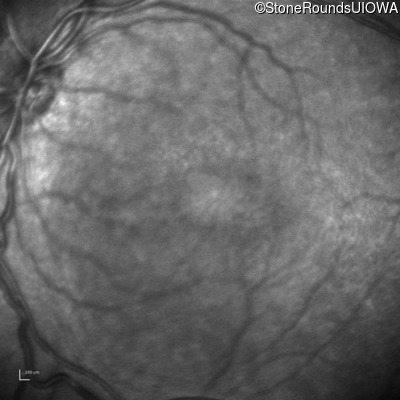

Infrared Fundus Photograph - Right - 10/40

Exemplar